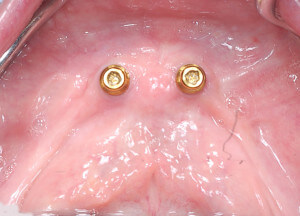

在下顎骨脊幾乎只剩一條線的狀況下,可以預見未來下顎活動假牙的穩定度一定很差.所以在治療的規劃裡,在下顎植了兩顆人工植體,利用植體去幫助假牙穩定.

DSC_3478